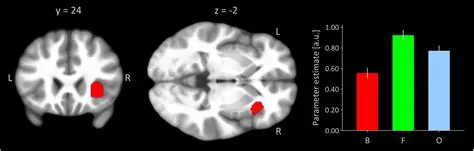

The Role of fMRI in Studying Sexual Arousal